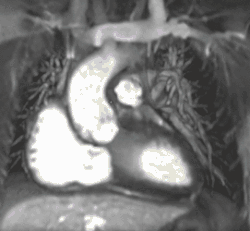

Heart function using cine imaging

Functional and structural information is acquired using bSSFP cine sequences. These are usually retrospectively-gated and have intrinsically high contrast in cardiac imaging due to the relatively high T2:T1 ratio of blood compared to myocardium. Images are typically planned sequentially to achieve the standard cardiac planes used for assessment. Turbulent flow causes dephasing and signal loss allowing valvular disease to be qualitatively appreciated. The left ventricular short axis cines are acquired from base to apex and are used for quantifying end-diastolic and end-systolic volumes, as well as myocardial mass. Tagging sequences excite a grid pattern that deforms with cardiac contraction allowing strain to be assessed.